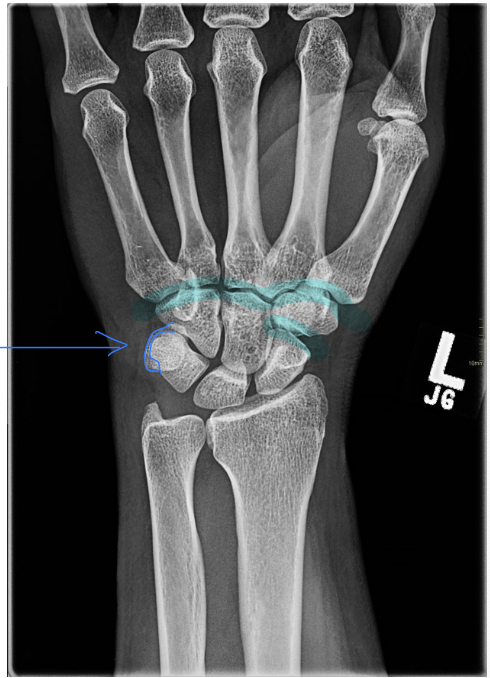

What is the positioning fault?

• scapholunate joint is closed (obliqued)

• trapezoid and trapezium are seperated

• thumb is away from IR

What causes foreshortening of the scaphoid

• radial deviation causes foreshortening - signet ring sign